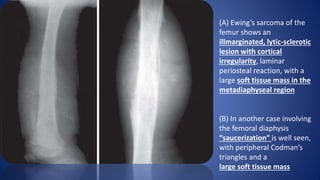

(A) Ewing’s sarcoma of the

femur shows an

illmarginated, lytic-sclerotic

lesion with cortical

irregularity, laminar

periosteal reaction, with a

large soft tissue mass in the

metadiaphyseal region

(B) In another case involving

the femoral diaphysis

“saucerization” is well seen,

with peripheral Codman’s

triangles and a

large soft tissue mass